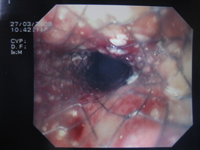

Prothèse oesophagienne endoscopique pour cancer

Au stade palliatif, le meilleur traitement de la dysphagie est la mise en place d’une prothèse oesophagienne par voie endoscopique. |